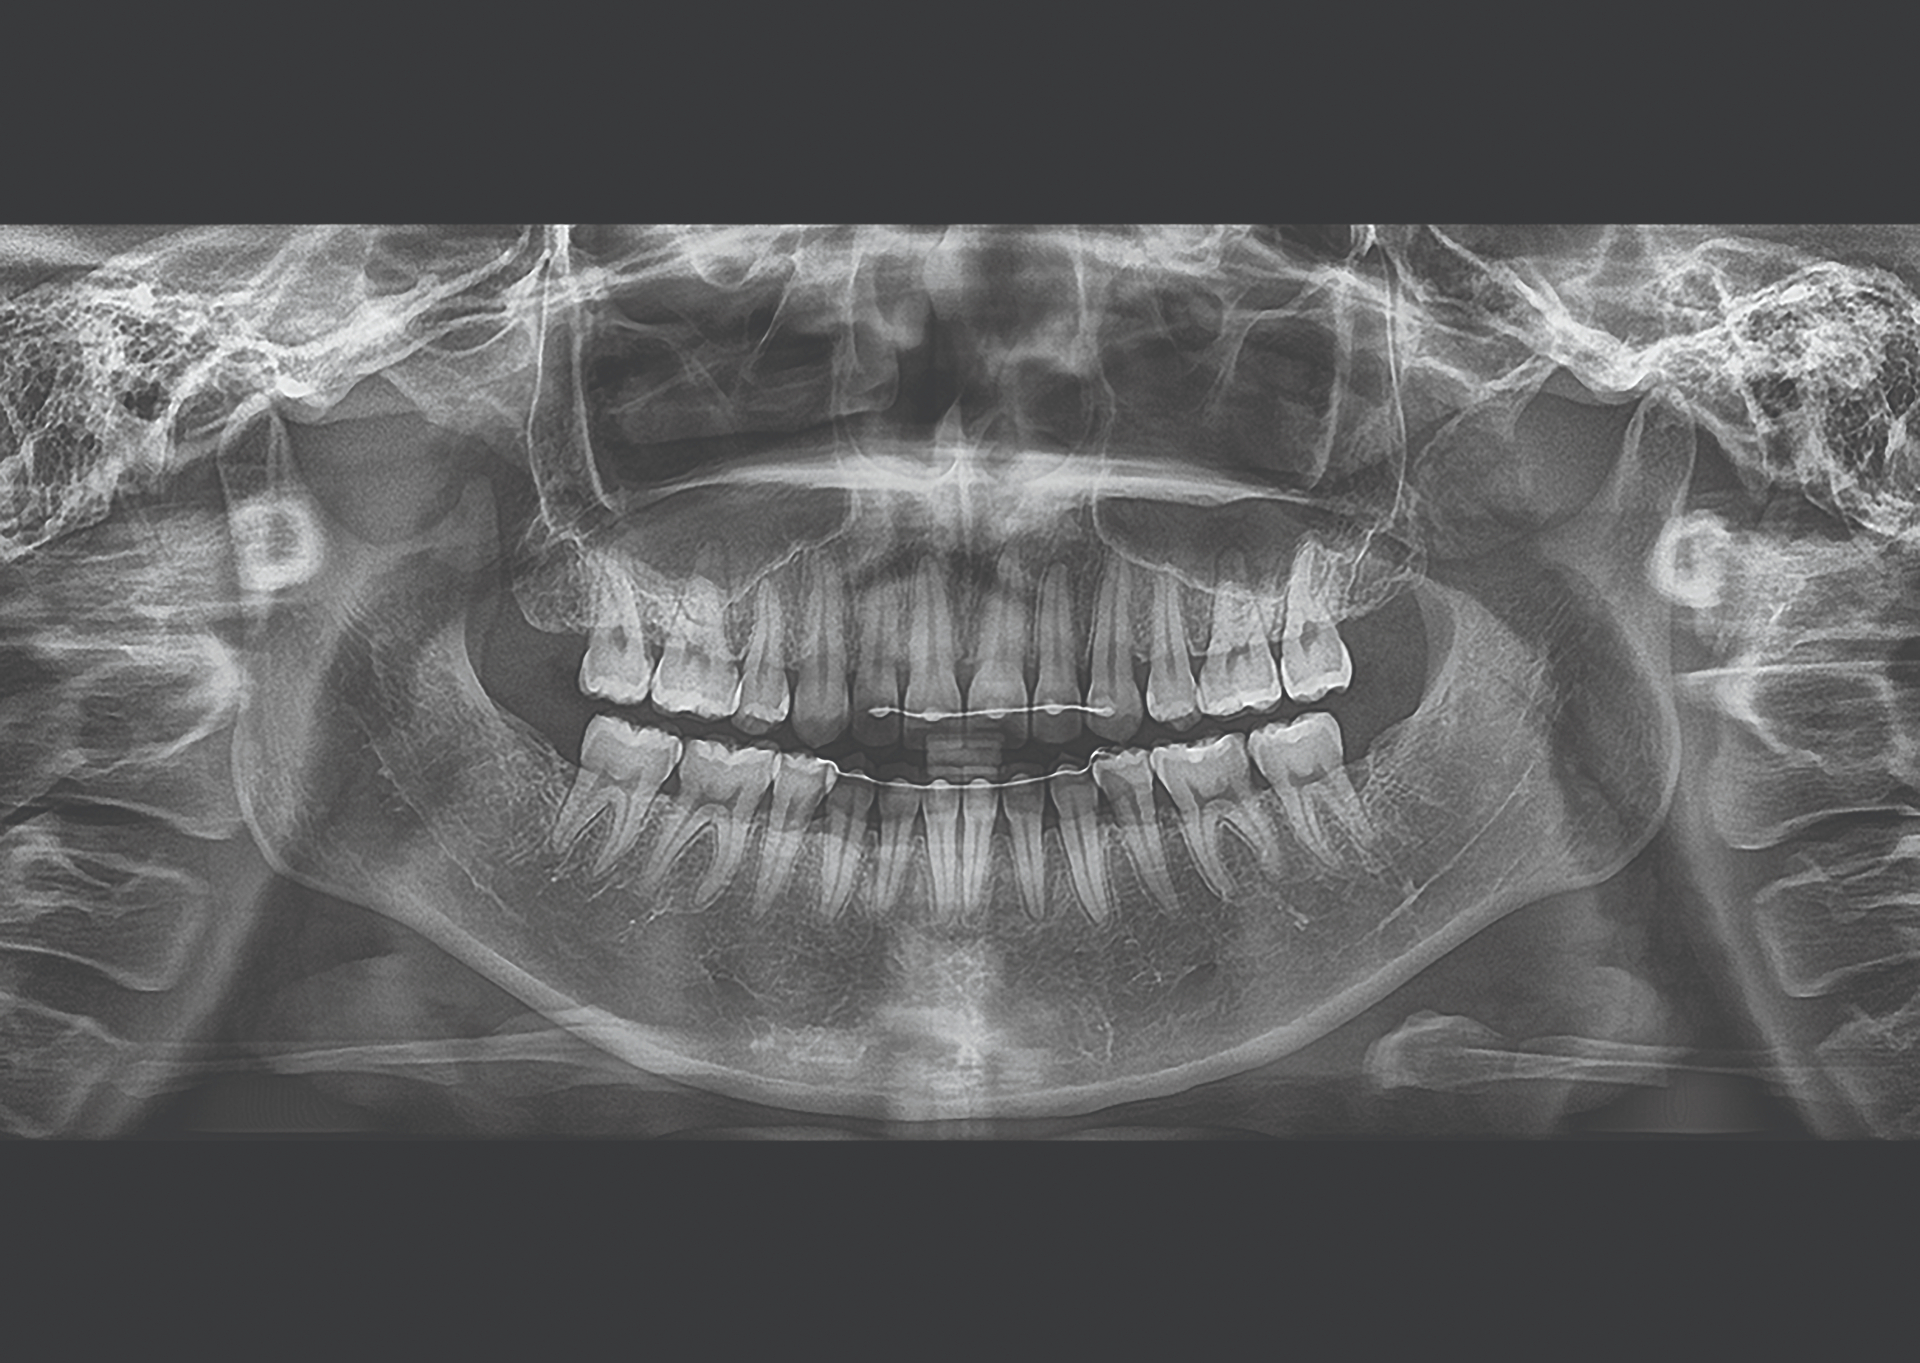

Master CBCT Implant Planning

Learn to plan dental implants with precision & confidence using CBCT imaging

A comprehensive live online masterclass for dentists looking to enhance their implant success rates